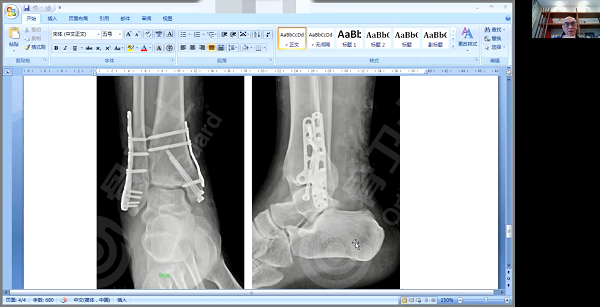

病例二

病例二是一位右内外踝骨骨折患者,男,45岁,因摔伤导致右踝内外踝关节内骨折。入院第三天,医院对患者进行解剖复位手术治疗,外踝采用接骨棒螺钉固定,内踝用空心拉力钉+钢板固定。

杨述华教授肯定了该患者治疗方案,他强调,踝关节内骨折治疗标准不存在功能复位,一定要达到解剖复位的标准。从影像资料看,该患者手术非常成功,适应征、手术方式选择得非常好,既达到了解剖复位,又促进了骨折愈合。由于该患者伴有软组织、肌腱损伤的情况,杨述华教授建议在手术后要用支具或石膏固定1-1.5个月。